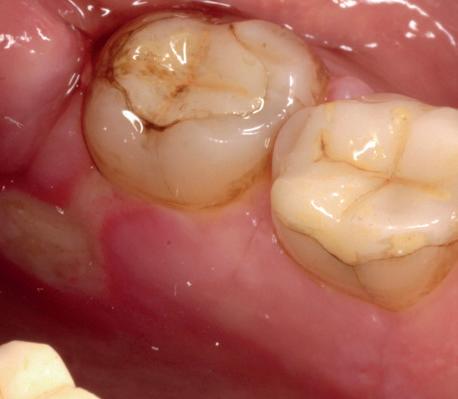

Casus

In deze casus is extractie van de 37 geïndiceerd in verband met een fistel en restpockets, zoals zichtbaar op de röntgenfoto’s (afbeelding 1). Duidelijk te zien is de forse peri-apicale ontsteking en het botverlies bij de 37, dat zowel richting buccaal als linguaal doorloopt. De 37 wordt atraumatisch verwijderd. Er is aan de linguale zijde veel bot verloren en er is sprake van een perforatie aan de buccale zijde.

Er wordt besloten om botmateriaal te plaatsen in de extractie-alveole. Vervolgens wordt het afgesloten met een titanium versterkt d-PTFE membraan (afbeelding 2). Na vier weken wordt het membraan verwijderd.

Zes maanden na extractie wordt het implantaat 37 geplaatst. Er is sprake van een goede genezing en de processushoogte en -breedte zijn behouden en opgebouwd. Ook is er zichtbaar gekeratiniseerd weefsel

1 2 Ridge preservation met d-PTFE membranen 35

gewonnen. De wond kan na het plaatsen van een healing abutment primair gesloten worden (Afbeelding 3a-3d).

In afbeeldingen 4a-c is het resultaat drie maanden na het plaatsen van het implantaat te zien. De genezing is volledig en de verwijzer kan de suprastructuur vervaardigen (afbeelding 4a-4c).

In afbeeldingen 5a-d is de implantaatkroon 37 te zien, twee jaar na plaatsing. Op de röntgenfoto is herstel van zowel corticaal als spongieus bot te zien. (De CB-CT was vervaardigd in verband met implantologische indicatie in het naastliggende gebied).